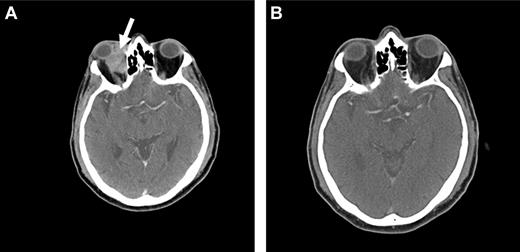

CT and magnetic resonance tomography (MRI) with contrast enhancement are the primary radiographic imaging tools in the evaluation of ocular adnexal proliferations. They aid in the assessment of location, size, and degree of infiltration; however, they cannot reliably distinguish between benign and malignant processes. Cuts of 1 to 3 mm are performed in axial and coronal planes, including the cavernous sinus and parasellar area to determine extraorbital extension. Typical imaging appearance of a lymphoid lesion is that of a unifocal, homogeneous, well-circumscribed lesion of isodensity to slight hyperdensity, with mild to moderate contrast enhancement, and smooth, distinct borders, molding into adjacent tissues and displacing rather than infiltrating orbital structures (Figure 3).55,56 Infiltration into the globe or bony erosions are unusual features of MALT lymphoma and should raise suspicion for high-grade transformation with aggressive clinical behavior.

Radiographic presentations of OAML. (A) CT image of right orbital MALT lymphoma involving the inferior rectus muscle, causing mild proptosis. (B) MRI of left orbital MALT lymphoma involving the lateral and inferior rectus muscles, causing medial deviation of the optic nerve, with involvement of the cavernous sinus (white arrow) and mild dural enhancement in the medial anterior cranial fossa (black arrow). Analysis of the cerebrospinal fluid was positive for lymphoma. This case represents an unusual extension of OAML into the central nervous system leading to lymphomatous meningitis.

Restrepo et al74 conducted a retrospective analysis exploring the need for central nervous system (CNS) prophylaxis in patients with OAL. In their study of 71 patients, including 54 with OAML, CNS prophylaxis was not administered, and none of the recurrences (15% after a median follow-up of 20 months) occurred in the CNS. The authors conclude that CNS prophylaxis in patients with OAL is unnecessary. However, very rare cases of CNS involvement can be observed (Figure 3B).